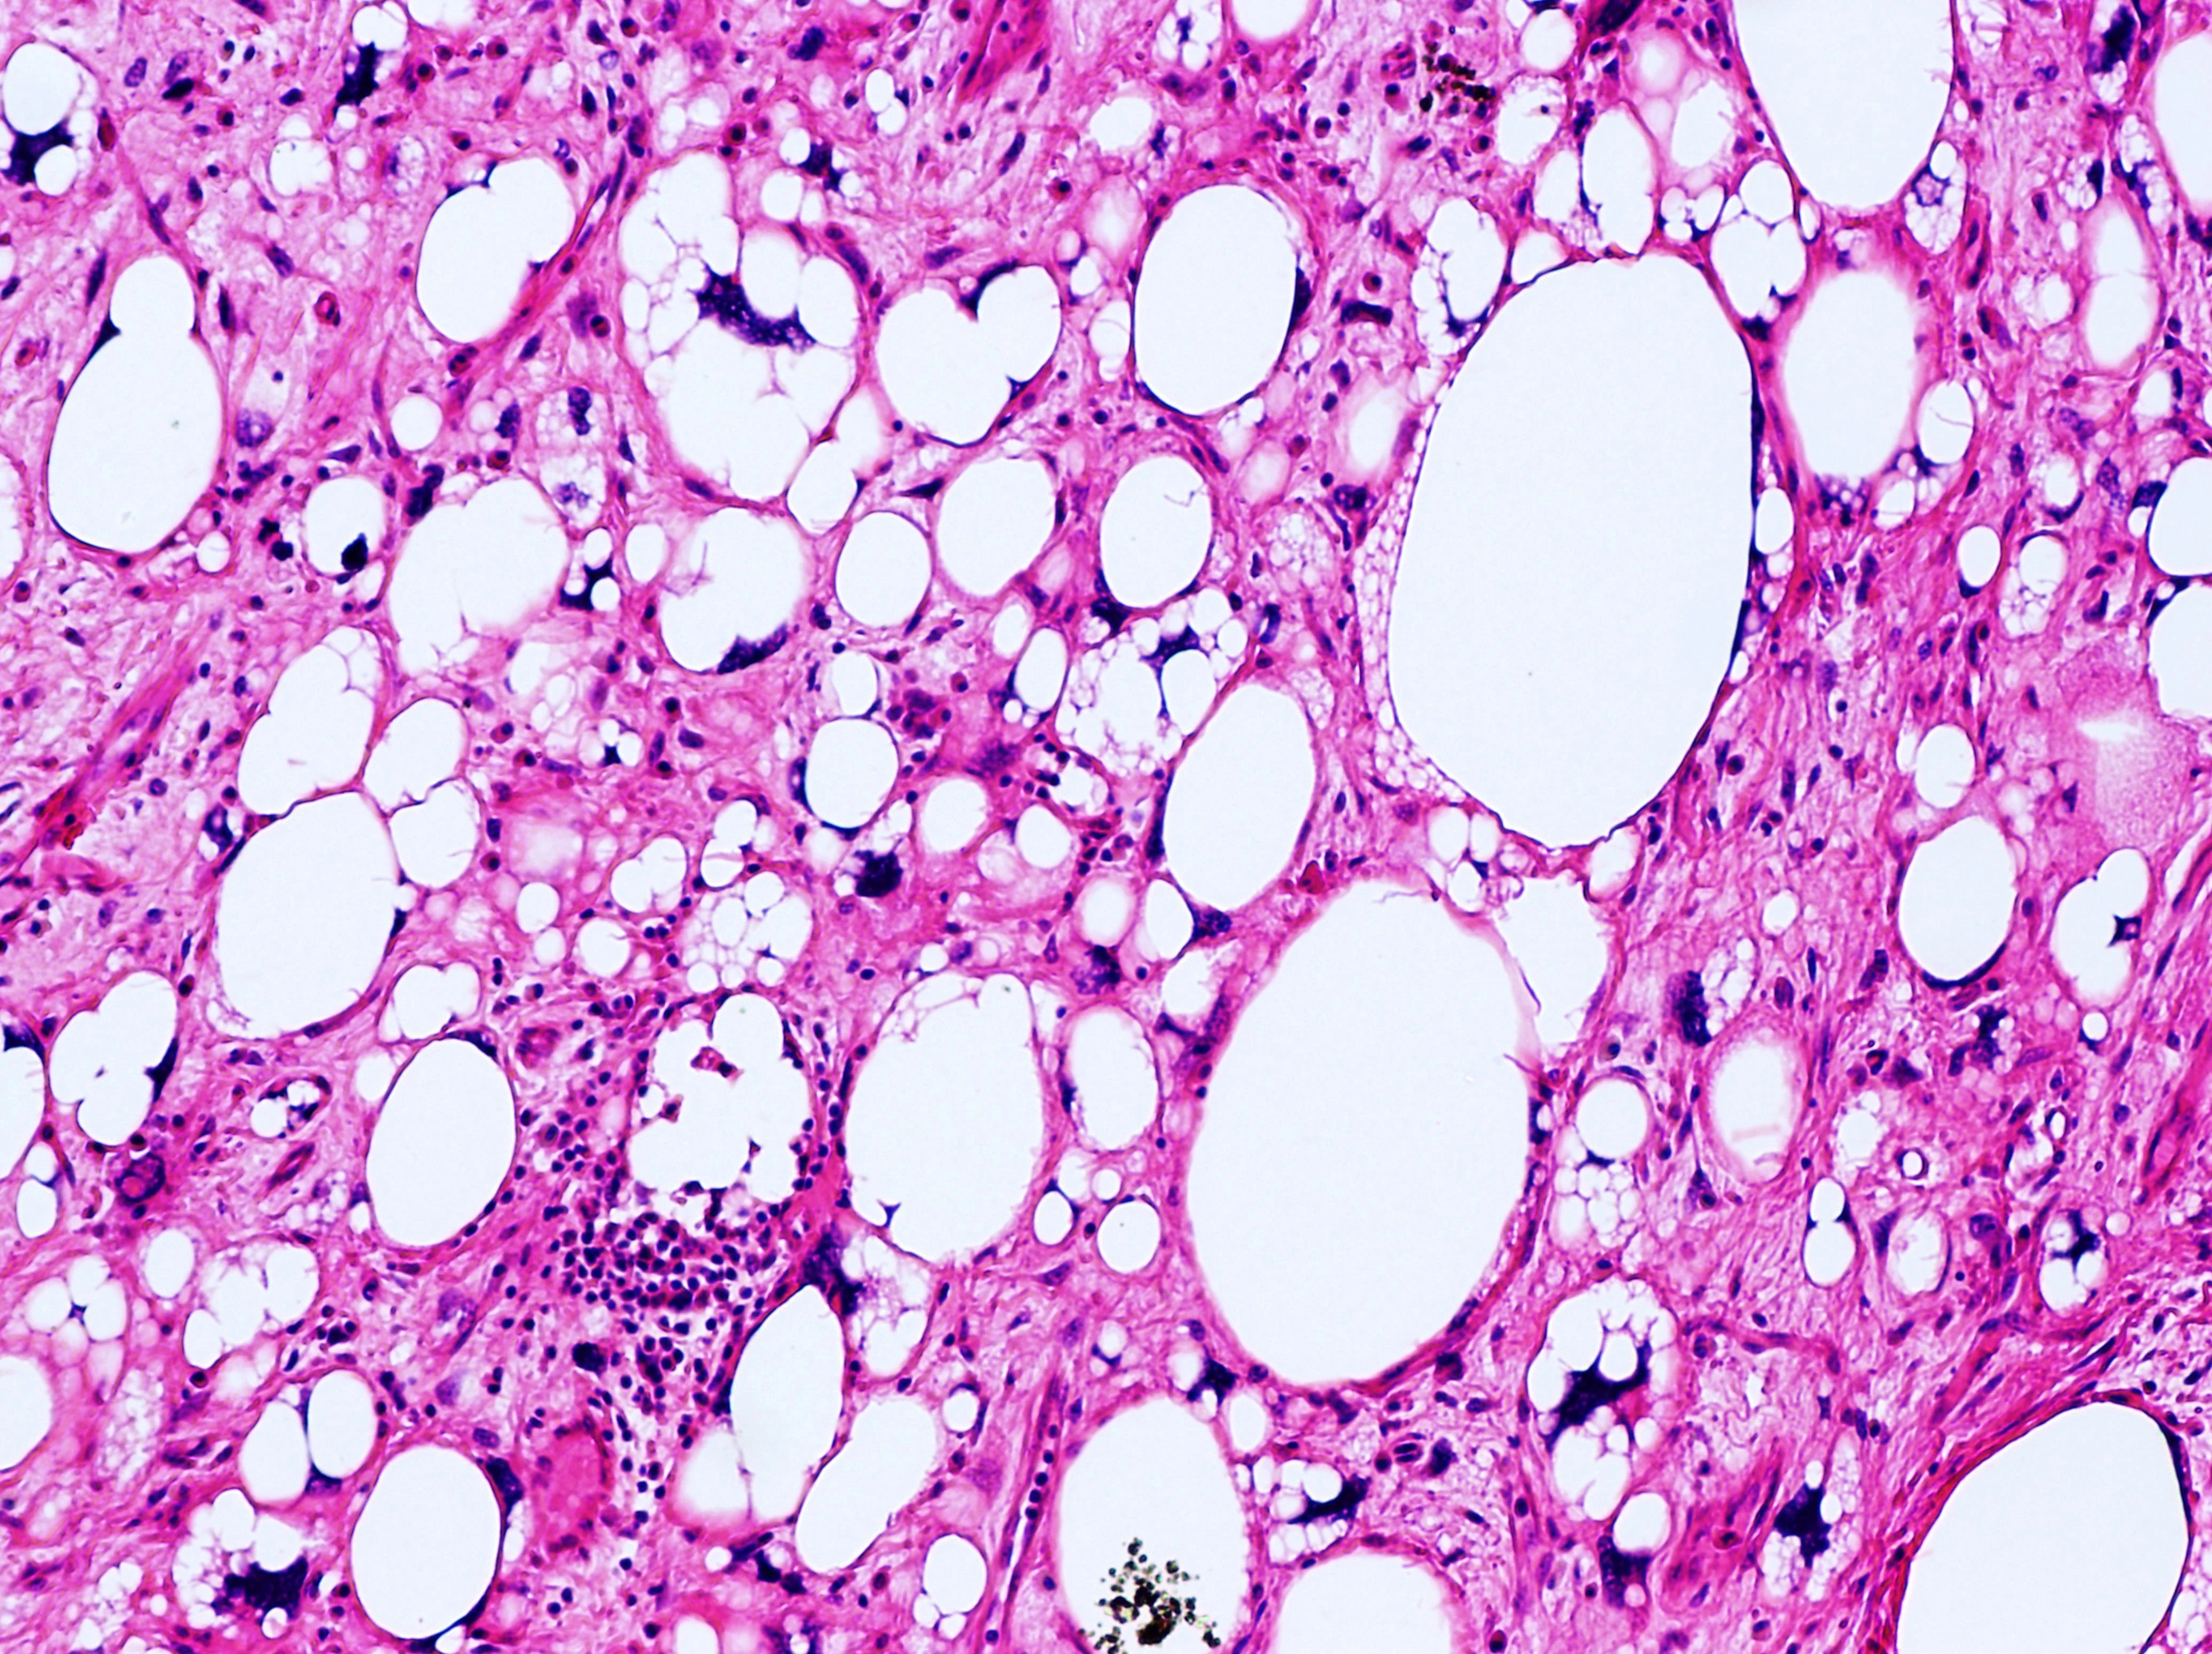

Atypical lipomatous tumor (well differentiated liposarcoma) with picture perfect lipoblasts.